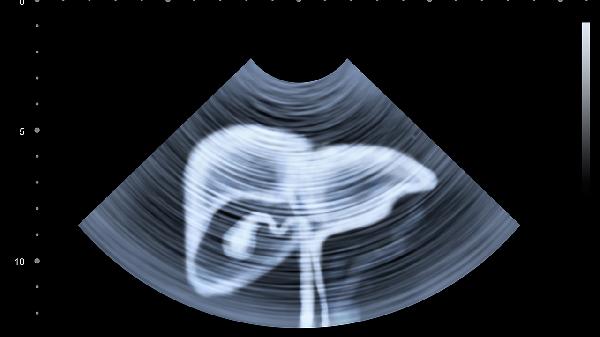

肝血管瘤是肝脏常见良性肿瘤,可能与雌激素水平或血管发育异常有关。多数无明显症状,较大血管瘤可能导致压迫性疼痛。通常通过超声或CT确诊,直径小于5厘米且无症状者可定期观察,必要时行介入栓塞治疗。